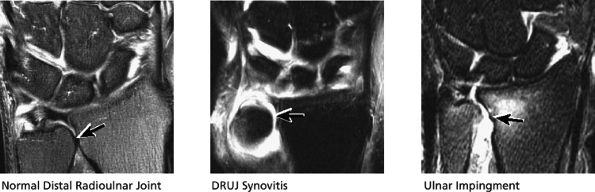

FIGURE 10.41 DISTAL RADIOULNAR JOINT.

The dorsal radioulnar ligament and palmar radioulnar ligament are the primary ligamentous stabilizers of the distal radioulnar joint and on axial plane images are seen coursing on both the dorsal and volar sides of the TFC, at the level of the base of the ulnar styloid, where the ligaments insert. Tears of the dorsal radioulnar ligament are associated with volar subluxation of the ulna. Tears of the volar radioulnar ligament are associated with dorsal subluxation of the ulna. Distal radioulnar joint instability is suggested when the ulnar head is abnormally subluxed or dislocated with respect to the radius, beyond the normal range of motion allowed for pronation and supination. In addition to ligamentous injury, osseous injuries such as fractures at the base of the ulnar styloid also may lead to distal radioulnar joint instability.